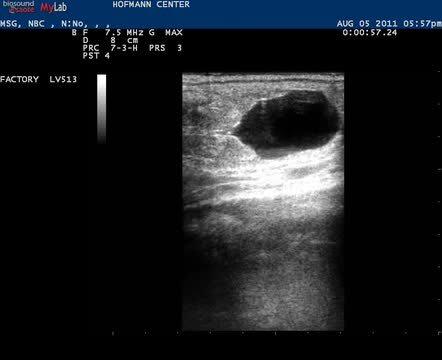

This video demonstrates a thorough examination that includes careful continuous imaging of the uterine body, each uterine horn, and its ipsilateral ovary. A 22-day conceptus was imaged that precluded this mare from having a complete breeding soundness examination.

Courtesy of Maria Schnobrich.